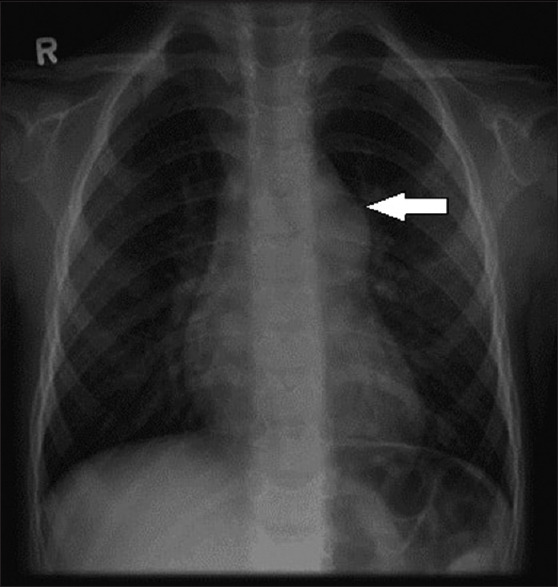

慢性血栓栓塞性肺动脉高压(Chronic thromboembolic pulmonary hypertension, CTEPH)是由于有组织血栓导致肺血管全部或部分闭塞而引起的,可导致严重的肺动脉高压,最终导致右心衰,这给麻醉治疗带来了很大的挑战。肺内膜切除术(PTE)是可手术CTEPH患者的治疗选择。本综述的目的是研究PTE后CTEPH患者的术前评估、麻醉技术和重症监护病房(ICU)的术后管理。我们从PubMed和谷歌Scholar数据库中检索了近25年来发表的期刊文章,关键词为“慢性血栓栓塞性肺动脉高压”、“肺血栓动脉内膜切除术的麻醉管理”和“CTEPH的围手术期管理”。共审查了153篇文章,最终检索到30篇。根据文献回顾,我们推断应谨慎选择平衡麻醉技术以避免血流动力学塌陷。经食管超声心动图(TEE)用于评估双室功能、肺动脉峰值压、三尖瓣反流严重程度、血栓位置及范围,指导肺动脉导管置入。深低温循环停止(DHCA)被用于执行一个完整的动脉内膜切除术到节段和亚节段动脉分支。这篇叙述性综述文章强调了麻醉师在术前评估、术中TEE指导、麻醉管理以及术后并发症(如再灌注肺水肿、残余肺动脉高压、肺内出血、DHCA和自由基损伤对CTEPH患者术后并发症的影响及预防,有待进一步研究。

Chronic thromboembolic pulmonary hypertension (CTEPH) is caused due to the total or partial occlusion of the pulmonary vasculature due to organized thrombus, leading to severe pulmonary hypertension and eventually right heart failure, which makes anesthetic management very challenging. Pulmonary endarterectomy (PTE) is the treatment of choice for patients with operable CTEPH. The objective of the present review is to examine the preoperative evaluation, anesthesia technique, and postoperative management in the intensive care unit (ICU) of patients with CTEPH after PTE. We identified published journal articles in the last 25 years from PubMed and Google Scholar databases with the keywords "chronic thromboembolic pulmonary hypertension,"" anesthetic management of pulmonary thrombo-endarterectomy," and "perioperative management of CTEPH." One hundred fifty-three articles were reviewed, out of which 30 articles were retrieved finally. Based on the articles reviewed, we inferred that a balanced anesthesia technique should be carefully chosen to avoid hemodynamic collapse. Transesophageal echocardiography (TEE) is used to assess biventricular function, peak pulmonary artery pressure, the severity of tricuspid regurgitation, location and extent of thrombus, and guide pulmonary artery catheter insertion. Deep hypothermic circulatory arrest (DHCA) is utilized to perform a complete endarterectomy into segmental and subsegmental arterial branches. This narrative review article highlights the role of anesthesiologists in preoperative evaluation, intraoperative TEE guidance, anesthetic management, and postoperative management of complications such as reperfusion pulmonary edema, residual pulmonary hypertension, intrapulmonary hemorrhage, and the consequences of DHCA in patients with CTEPH undergoing surgical PTE. Future research is required to study the effects of DHCA and free radical injuryon postoperative complications and its prevention.